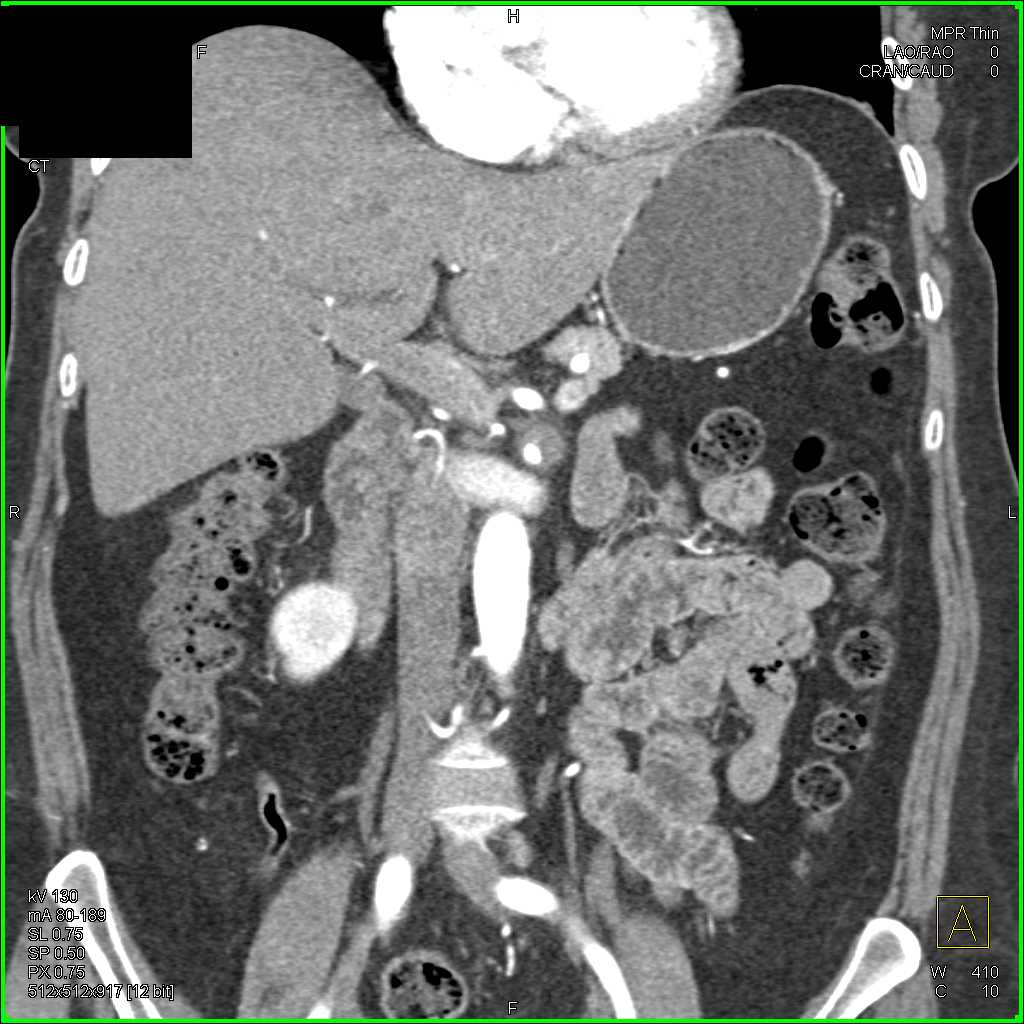

Neuroendocrine Tumor Body of Pancreas